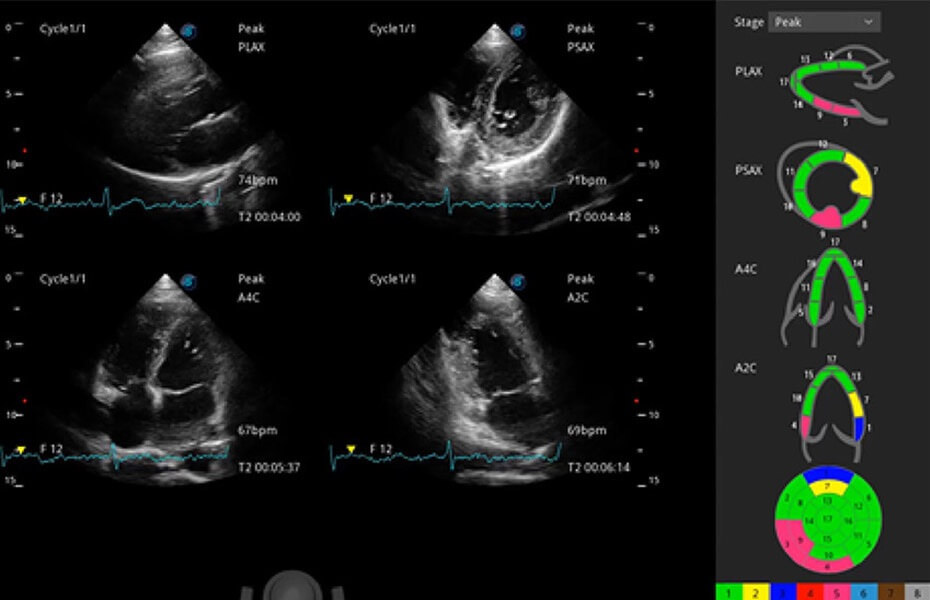

ProPet 60 作為一款高端臺式動物超聲設(shè)備,為動物醫(yī)生的日常診斷提供了一系列貼合動物臨床需求、解決臨床實(shí)際問題的高級成像功能。憑借全系列高清探頭,滿足醫(yī)生對腹部、心臟、生殖、淺表、肌骨等成像的所有需求,切實(shí)幫助您提升檢查效率,提高診斷信心。